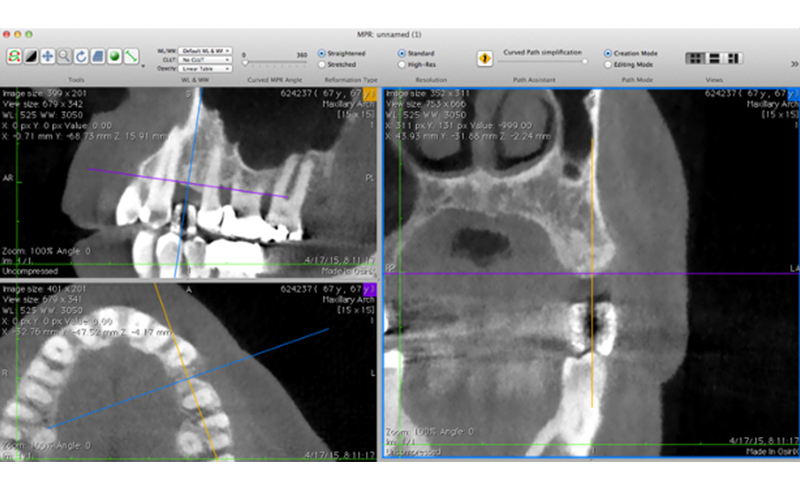

- 院内に設置したCTスキャナーで診査に必要な画像データを取得します。

- コンピュータで画像処理された立体の断層撮影画像やパノラマ画像を精査し、歯だけでなく顎の骨の健康状態やサイズ、神経の位置などを精密に診査します。

- CTスキャナーのデータを観察しただけでは手術は開始しません。精査したデータを基にコンピュータ上で手術のシミュレーションを行い、埋め込むインプラントのサイズ、形状、位置、角度などを検討して手術の計画を作ります。

インプラントは治療の前にCT検査による精密検査が必要です。歯を失った部位の骨幅、骨質等の状態、解剖学的に大切な脈管、神経、上顎洞との距離を把握する必要があります。

インプラント埋入前にCT写真の撮影は必ず行います。歯を失った部位の骨幅、骨質等の状態、解剖学的に大切な脈管、神経、上顎洞との距離を把握する必要があります。

これらの解剖を把握した上で個々の症例に合った適切なインプラントのサイズを決定したり、必要であれば骨量を増加させる処置の有無を決定します。

インプラント手術前には必ずCT写真の撮影を行い、適切な骨量の有無を検査します。

予定したインプラントのサイズに対して骨量が足りないケースでは歯槽堤増大術を推奨しています。

これによりインプラントの露出を防ぎ、インプラント周囲炎の予防に繋がります。

| 治療内容 | 左上臼歯1本にインプラント治療を施した1例。 術前のCT検査で骨の欠損部があったため(左図)、歯槽堤増大術を行ないました(右図)。これにより適切な位置にインプラントの埋入を計画することができます。 |

| 治療内容 | 右上小臼歯1本に インプラント治療を施した1例。 術前のCT検査で骨の欠損部があったため(左図)、歯槽堤増大術を行ないました(右図)。これにより適切な位置にインプラントの埋入を計画することができます。 |

| 治療内容 | 右下小臼歯1本に インプラント治療を施した1例。 術前のCT検査で骨の欠損部があったため(左図)、歯槽堤増大術を行ないました(右図)。これにより適切な位置にインプラントの埋入を計画することができます。 |

| 治療内容 | 右上前歯1本に インプラント治療を施した1例。 術前のCT検査で骨の欠損部があったため(左図)、歯槽堤増大術を行ないました(右図)。これにより適切な位置にインプラントの埋入を計画することができます。 |

| 治療内容 | 左上大臼歯1本にインプラント治療を施した1例。 術前のCT検査で骨の高さ不十分であったため(左図)、上顎洞挙上術を行ないました(右図)。これにより適切な位置にインプラントの埋入を計画することができます。 |

| 治療内容 | 右上大臼歯1本にインプラント治療を施した1例。 術前のCT検査で骨の高さ不十分であったため(左図)、上顎洞挙上術を行ないました(右図)。これにより適切な位置にインプラントの埋入を計画することができます。 |